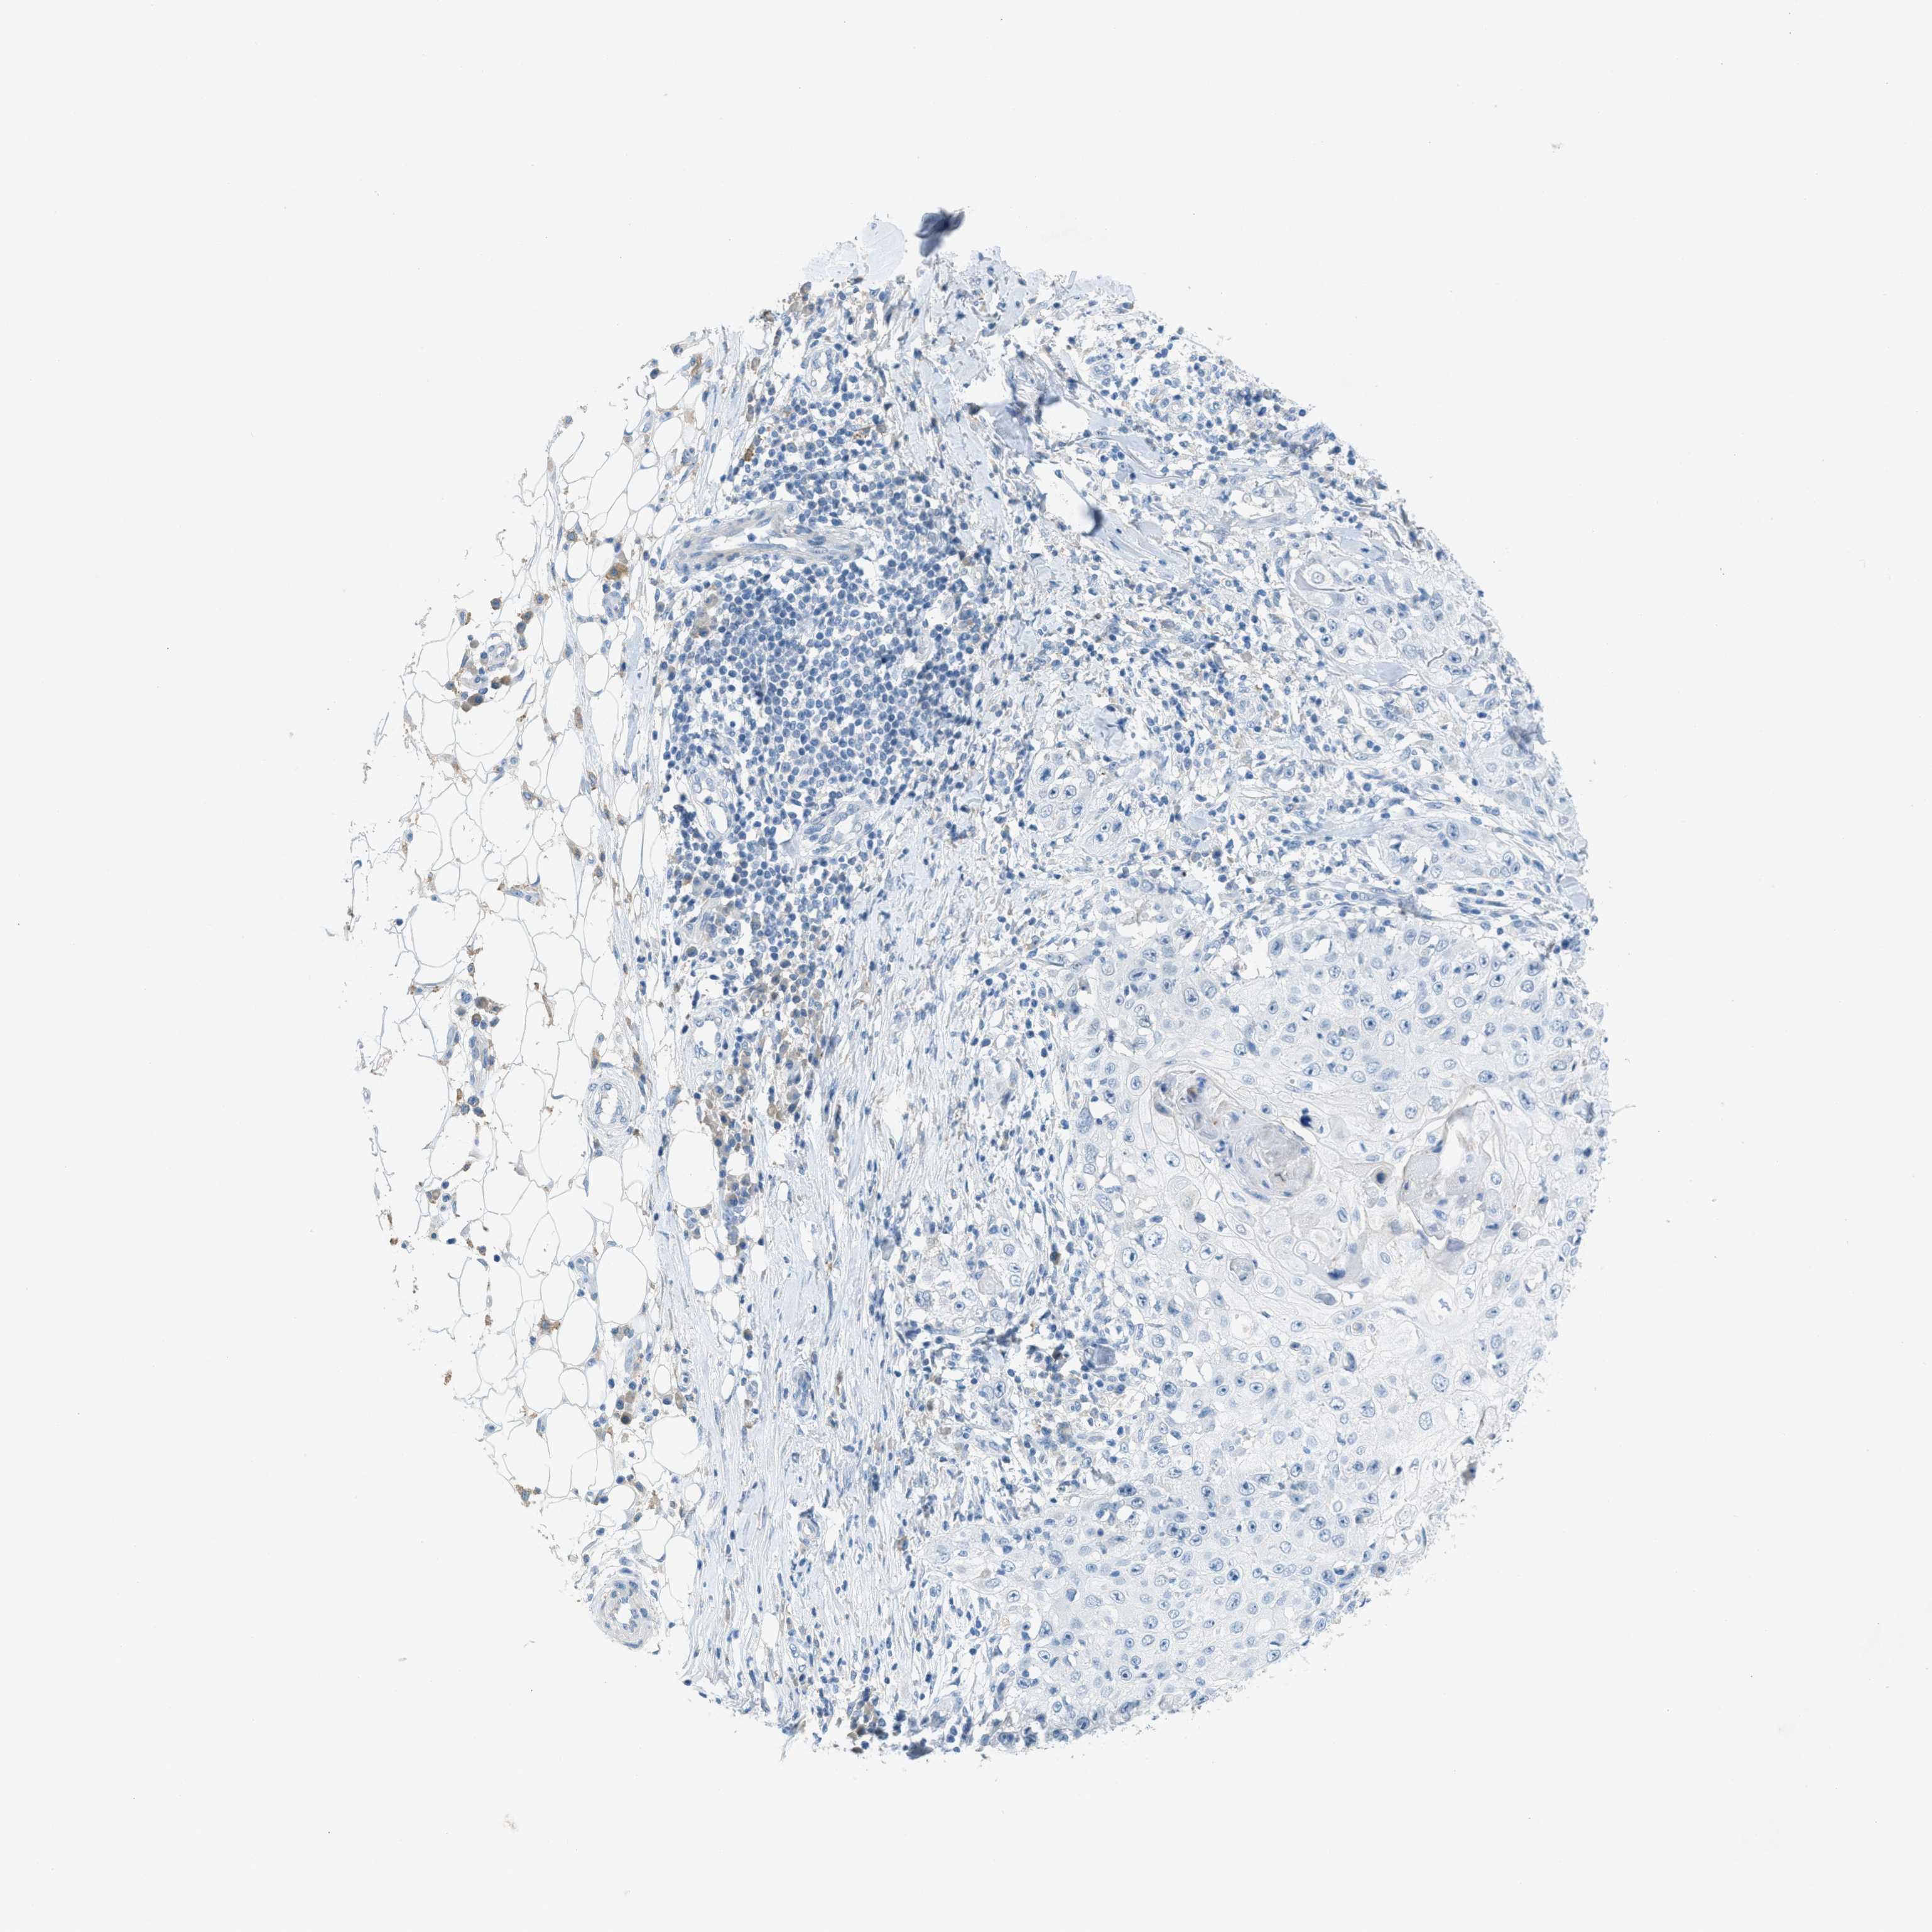

SKIN CANCER - Protein expressioni

A mouse-over function shows sample information and annotation data. Click on an image to view it in a full screen mode. Samples can be filtered based on level of antibody staining by selecting one or several of the following categories: high, medium, low and not detected. The assay and annotation is described here.

Each image is clickable and will lead to virtual microscopy that enables deeper exploration of all samples and also displays staining intensity scores, fraction scores and subcellular localization as well as patient and tissue information for each sample.

Antibody HPA013856

Antibody HPA017762

Squamous cell carcinoma, NOS

Basal cell carcinoma

Squamous cell carcinoma in situ, NOS

Squamous cell carcinoma, metastatic, NOS